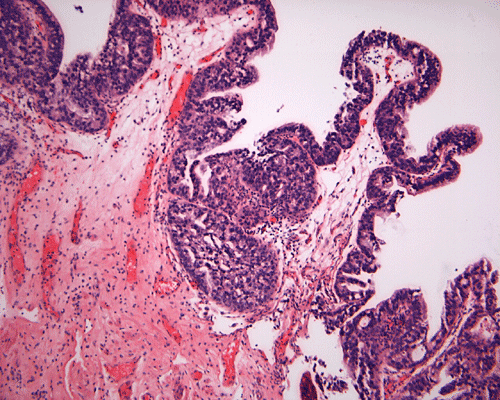

A. B. C. D. E.

On scanning-magnification, the biopsy material consists of small nodules of stromal tissue with epithelium lined papillae (Panel A). On low-magnification (Panel B), both multilayered epithelium  and cribiform pattern (Panel C)are demonstrated. On high-magnification  (Panel D), the epithelial cells are hyperchromatic and pleomorphic. Intracytoplasmic mucin is well demonstrated by periodic acid-Schiff (PAS)- Alcian blue stain (Panel E) and mucicarmine stain (Panel F). No invasion is demontsrated.

Histologically, in situ adenocarcinoma is defined as a noninvasive glandular lesion, where the mucosa of the urinary bladder is replaced by an atypical, often pseudostratified columnar epithelium, featuring atypical cytoplasm and definitive cytologic atypia with nuclear hyperchromasia, moderate to severe nuclear pleomorphism, frequent mitosis and apoptosis 4. Necrosis is infrequently seen.

Three distinct architectural patterns have been described: papillary, cribriform and flat 2, 3, 4. Papillary architecture is the one most commonly seen, followed by cribriform pattern. Individual cases rarely show a pure pattern; rather, various combinations of the three patterns are more often seen.